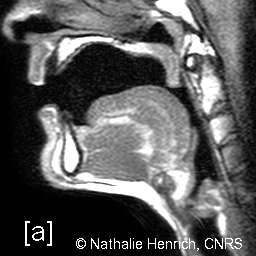

Pour étudier la voix, Nathalie Henrich utilise toute une panoplie d’instruments de mesure et de visualisation, le but final étant de comprendre l’utilisation des différents organes vocaux et leurs effets sans trop les perturber. « Chaque technique possède ses avantages et ses inconvénients. Par exemple, dans une endoscopie par le nez, nous visualisons des mouvements articulatoires internes en fond de gorge, mais nous ne pouvons pas voir finement la vibration des plis vocaux (ou cordes vocales). Mais une endoscopie par la bouche va gêner l’articulation, mais permettre de visualiser avec précision la vibration glottique. L’IRM ou les ultrasons sont des techniques moins invasives, mais dans le premier cas, la personne étudiée doit être couchée, et dans le second, la portée est limitée. » Le son de la voix peut lui aussi être disséqué grâce à un traitement du signal. Cependant, qu’elle soit chantée ou parlée, la voix humaine recèle encore de secrets à découvrir.